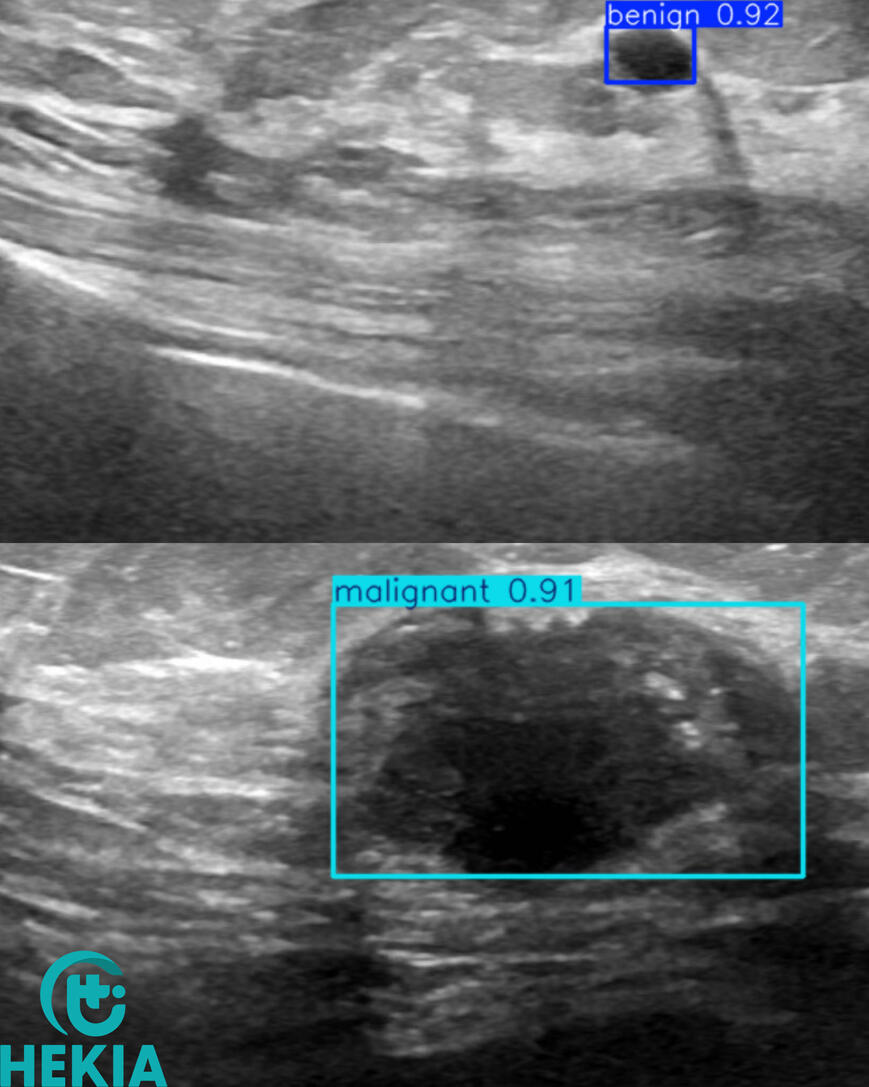

AI for ultrasound detection

Hekia is involved with Professor Fumery (CHU-Amiens-Picardie/UPJV) in the ECHIA-IBD1 project for real-time detection of Crohn's disease. The aim of this project is to speed up diagnosis by non-specialists in IBD ultrasound, make digestive tract ultrasound more accessible for monitoring Crohn's disease and UC activity, and improve patient outcomes.